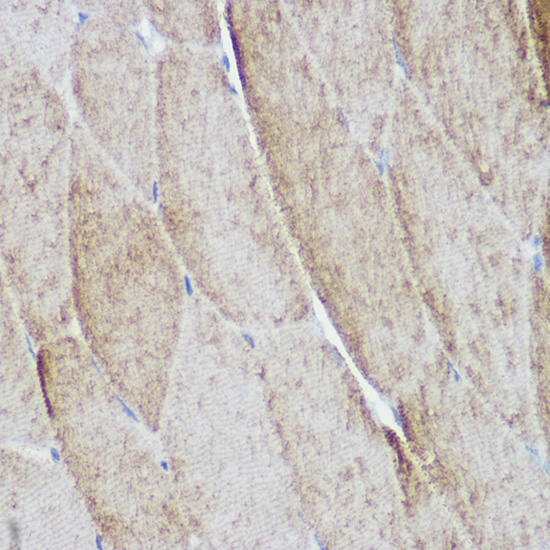

Immunohistochemistry of paraffin-embedded mouse skeletal muscle using ACTN3 Rabbit pAb.

Immunohistochemistry of paraffin-embedded rat skeletal muscle using ACTN3 Rabbit pAb.